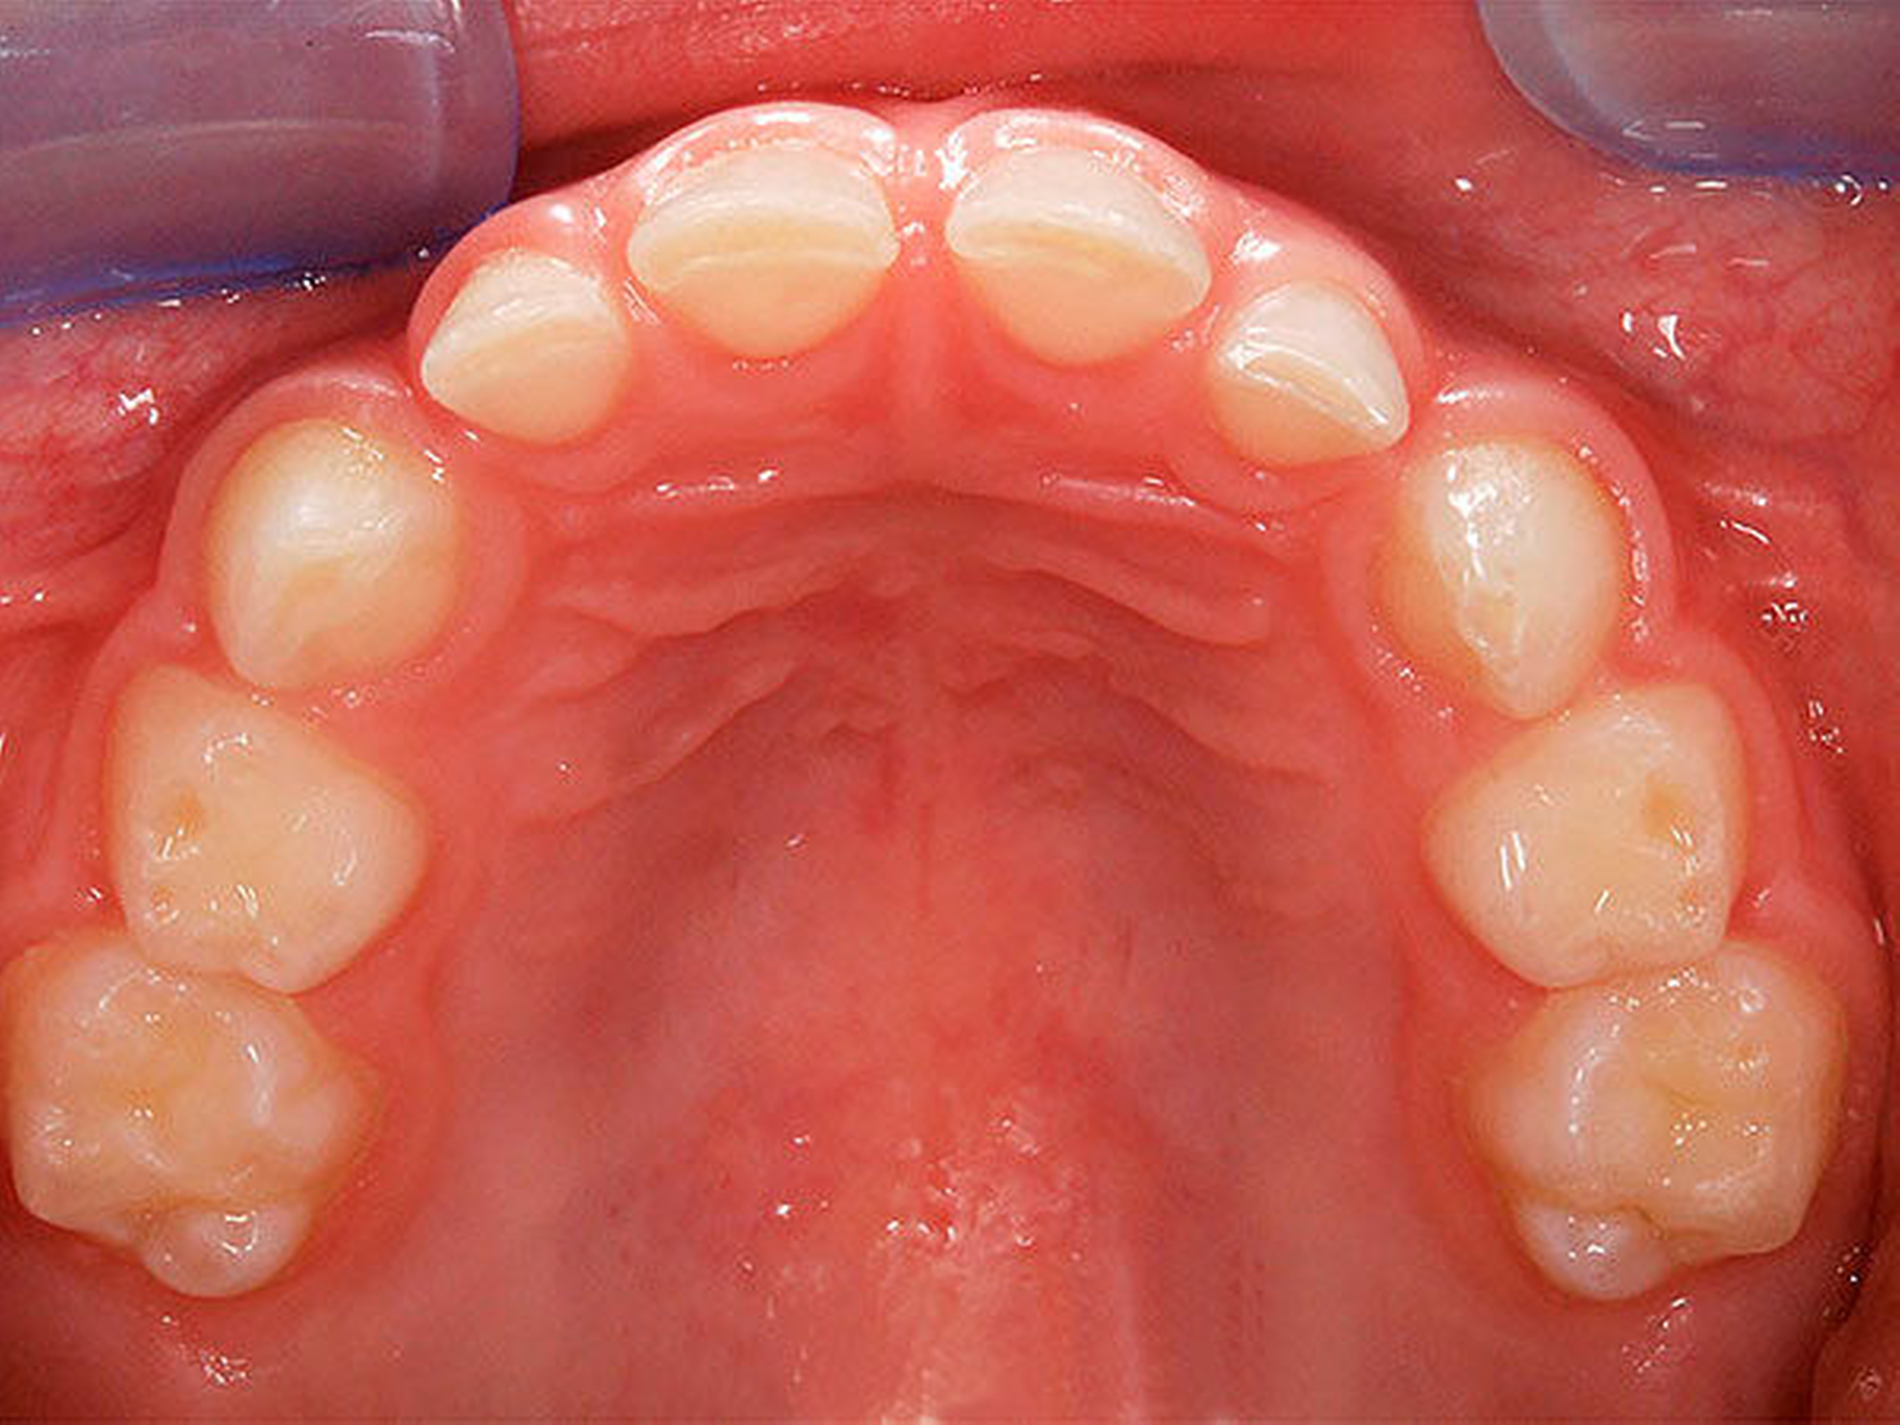

Besonders wichtig ist aus zahnärztlich-kieferorthopädischer Sicht die Beurteilung der lateralen Okklusionsverhältnisse [Kahl-Nieke, 2015]. Der unilaterale Kreuzbiss kommt ungefähr viermal häufiger vor als der bilaterale [Schopf, 2003]. Bei 80 Prozent der Kinder mit einseitigem Kreuzbiss tritt eine funktionelle Unterkieferabweichung auf [Kurol, 1992] und die Unterkiefermitte verschiebt sich dabei zur Kreuzbissseite [Santos Pinto, 2001] bei gleichzeitig asymmetrischer Kondylenposition. Diese reflektorische Einnahme der Kreuzbissstellung vergrößert die Anzahl der Okklusionskontakte, mit der Gefahr, dass nach kurzer Zeit diese transversale Fehlstellung des Unterkiefers neuromuskulär fixiert wird. Bei Belassen des Kreuzbisses kann eine skelettale Manifestation der Asymmetrie und eine dauerhafte Abweichung der Kinnmitte von der Gesichtsmitte resultieren [Hesse, 1997; O`byrn, 1995]. Erfolgt keine frühzeitige Therapie, besteht zudem die Gefahr einer Wachstumshemmung im Bereich der im Kreuzbiss „eingefangenen“ Oberkieferseite. Eine kieferorthopädische Frühbehandlung scheint präventiv gegen eine skelettale Adaptation und gegen eine Persistenz des Kreuzbisses in die permanente Dentition zu wirken [Harrison, 2001]. Das Überstellen des lateralen Kreuzbisses durch transversale Weitung des Oberkiefers kann beispielsweise mittels forcierter Gaumennahterweiterung [Köbel, 2017] erfolgen und wirkt sich neben einer Verbesserung der respiratorischen Situation günstig auf die Beseitigung skelettaler und dentoalveolärer Asymmetrien aus [Hesse, 1997; Santos Pinto, 2001] (Abbildung 3).